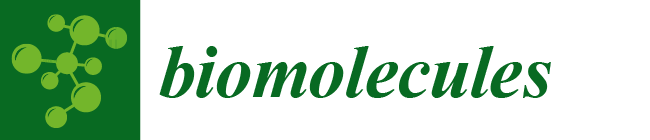

2.2. OCT Images and Scans of Pixel Intensity Versus Depth Measurements

2.3. Measurement of Resonant Frequency and the Elastic Modulus